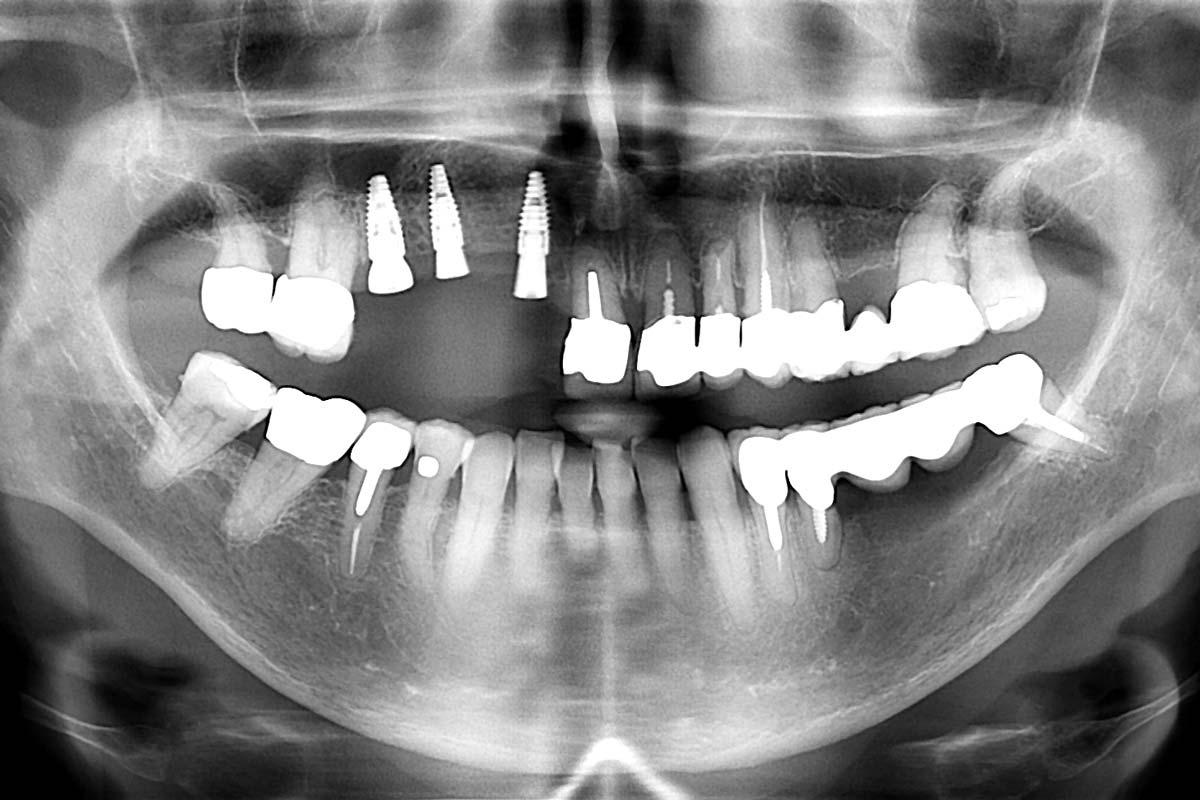

Preoperative situation – Maxillary defect in area 14-16 (loss of implant 16 due to periimplantitis, tooth 14 extracted recently and area 15 already edentulous for a while)

Initial x-ray, ten years post implantationem alio loco, large peri-implant bone loss

Initial clinical situation: Bone defect in the upper right maxilla (teeth #14-16)